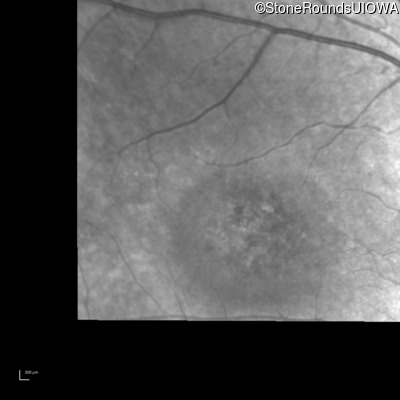

Infrared Fundus Photograph - Left - 20/200

Exemplar